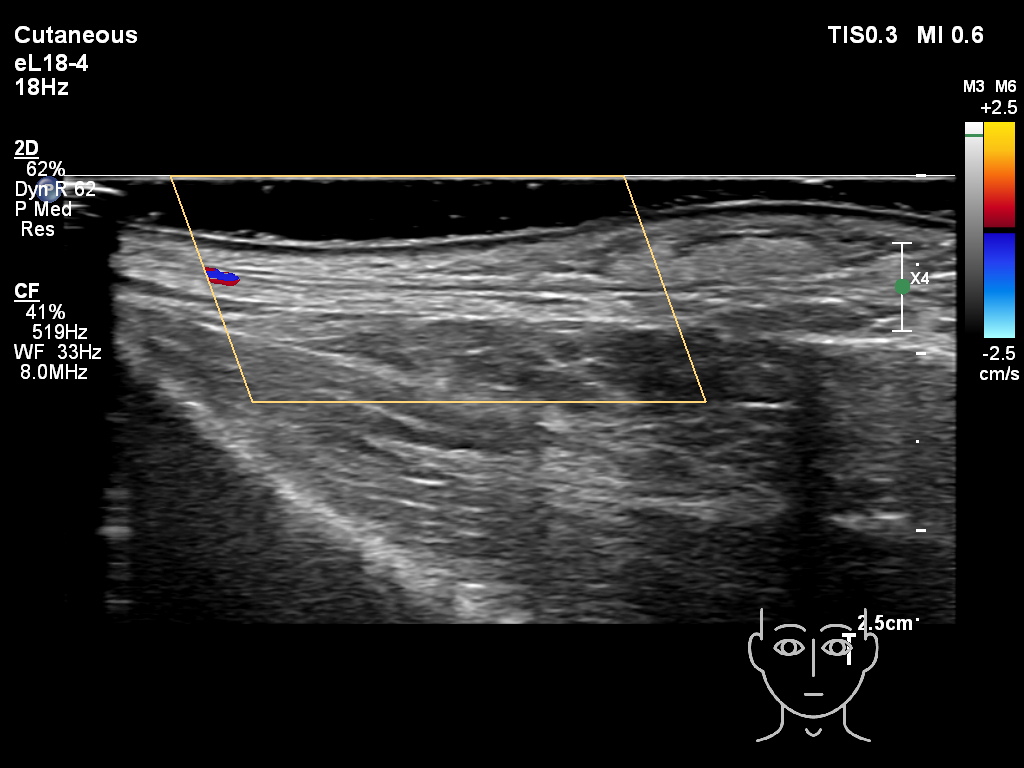

Draw in the image on the right where the fillers are located. To check if your answer is correct, please click on the secondary image.

Draw in the second image below where the fillers are located. To check if your answer is correct, swipe the first image to the right.